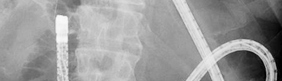

胆道膵管造影(ERCP)

超音波内視鏡(EUS)

消化管ステント

バルーン内視鏡を用いたERCP